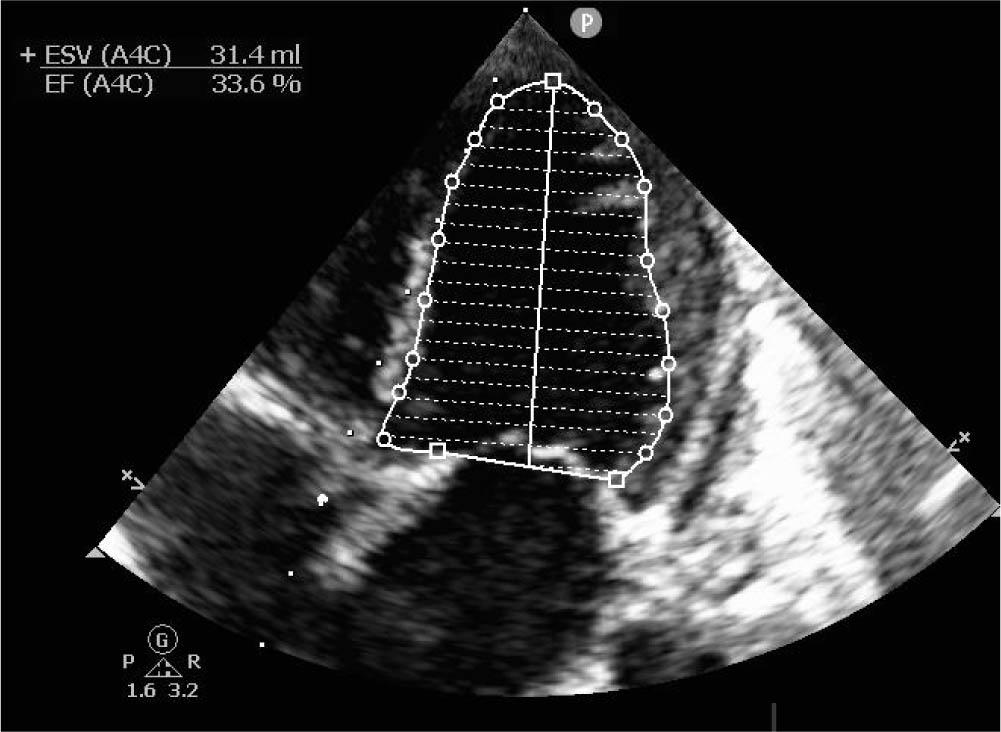

Figure 1